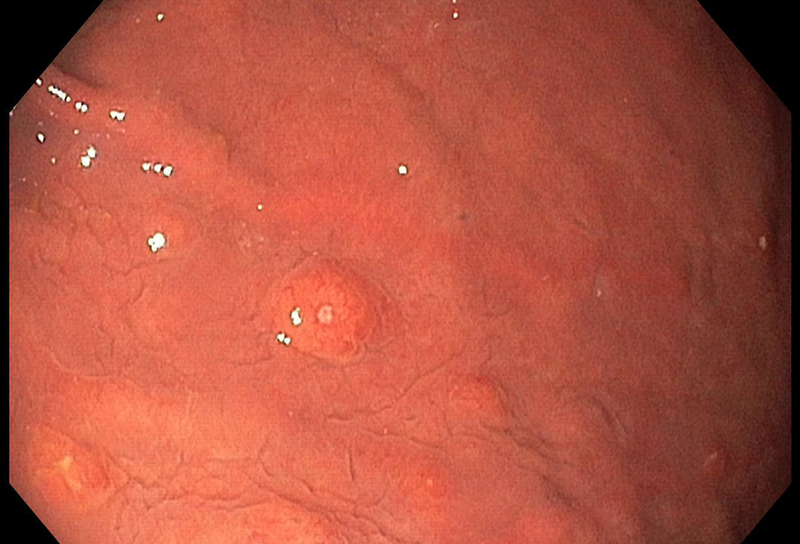

A 67-year-old male underwent endoscopic evaluation of the upper gastrointestinal tract after diagnosis of peritoneal carcinomatosis in the setting of unknown primary on CT scan (CUP syndrome). Within the gastric corpus, MULTIPLE nodular (sub)mucosal lesions, some of which with volcano-like central ulceration, were seen (Panels A-B). In addition to biopsy sampling, endoscopic mucosal resection (EMR) of the largest lesion was performed.